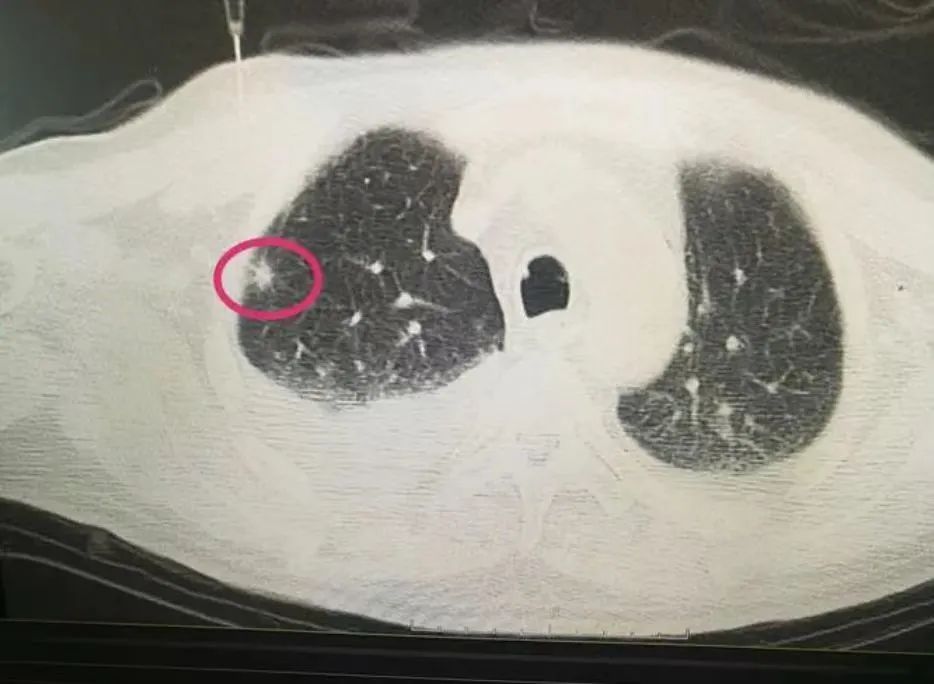

3、影像学检查:这是发现和鉴别肺部结节的主要方法,包括胸部X线片、胸部CT等。胸部CT是肺部疾病最常用的检查方法。常规CT扫描通常用于筛查高危人群,而增强CT扫描通常用来诊断肺结节的边缘、密度、钙化和周围关系,为确定肺结节的性质提供基础。

4、肺穿刺检查:这是临床诊断肺部结节和肿块的重要手段,对明确肺部结节的性质具有重要的诊断价值。

5、电磁导航系统CT引导下经皮肺活检:在电磁导航系统下,可以准确定位穿刺点,减少穿刺次数,缩短穿刺时间,降低CT辐射剂量。